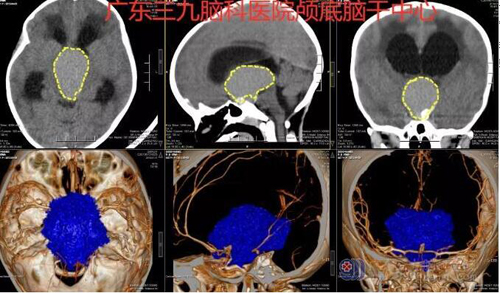

图1:鞍上区占位性病变,其内示小片状极高密度钙化影,未见明确血管影,邻近WILLIS环血管受压明显扩大。